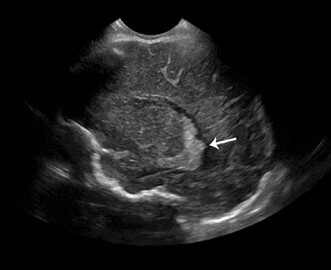

Neonatology Choroid Plexus Lobulation 1 Image